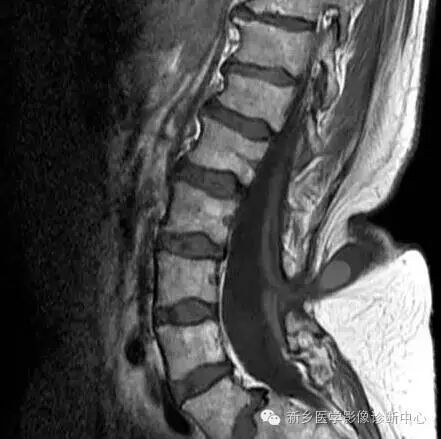

脊柱MRI提示椎管内占位及相应水平椎体后缘扇贝样压迹(白箭)

椎体后缘扇贝压迹征为脊柱侧位X线中,一个或多个椎体后缘呈扇贝样凹陷改变。

椎体后缘生理情况下可见轻度凹陷改变,但单发或多发的扇贝样压迹主要见于椎管内病变向前压迫累及或椎体本身骨质异常。

单发的扇贝样压迹最常见的原因为椎管内肿瘤引起椎管内压力增高,局部 向前压迫椎体后缘所致,如室管膜瘤、神经鞘瘤。